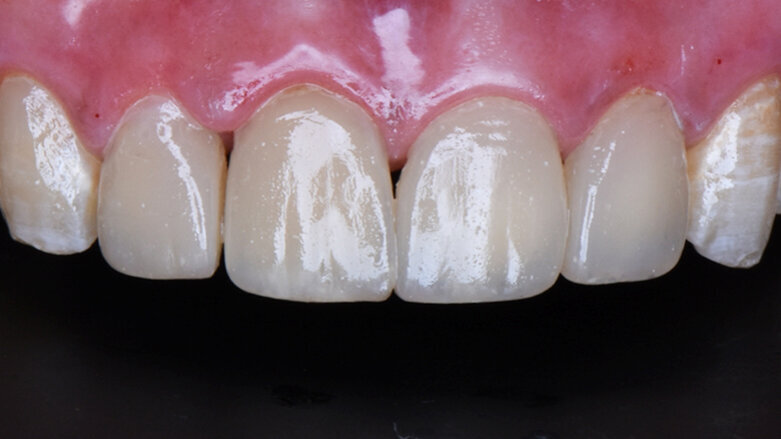

After

Step 8 – Post operative view Highly aesthetic outcome using (ceram.x® duo).